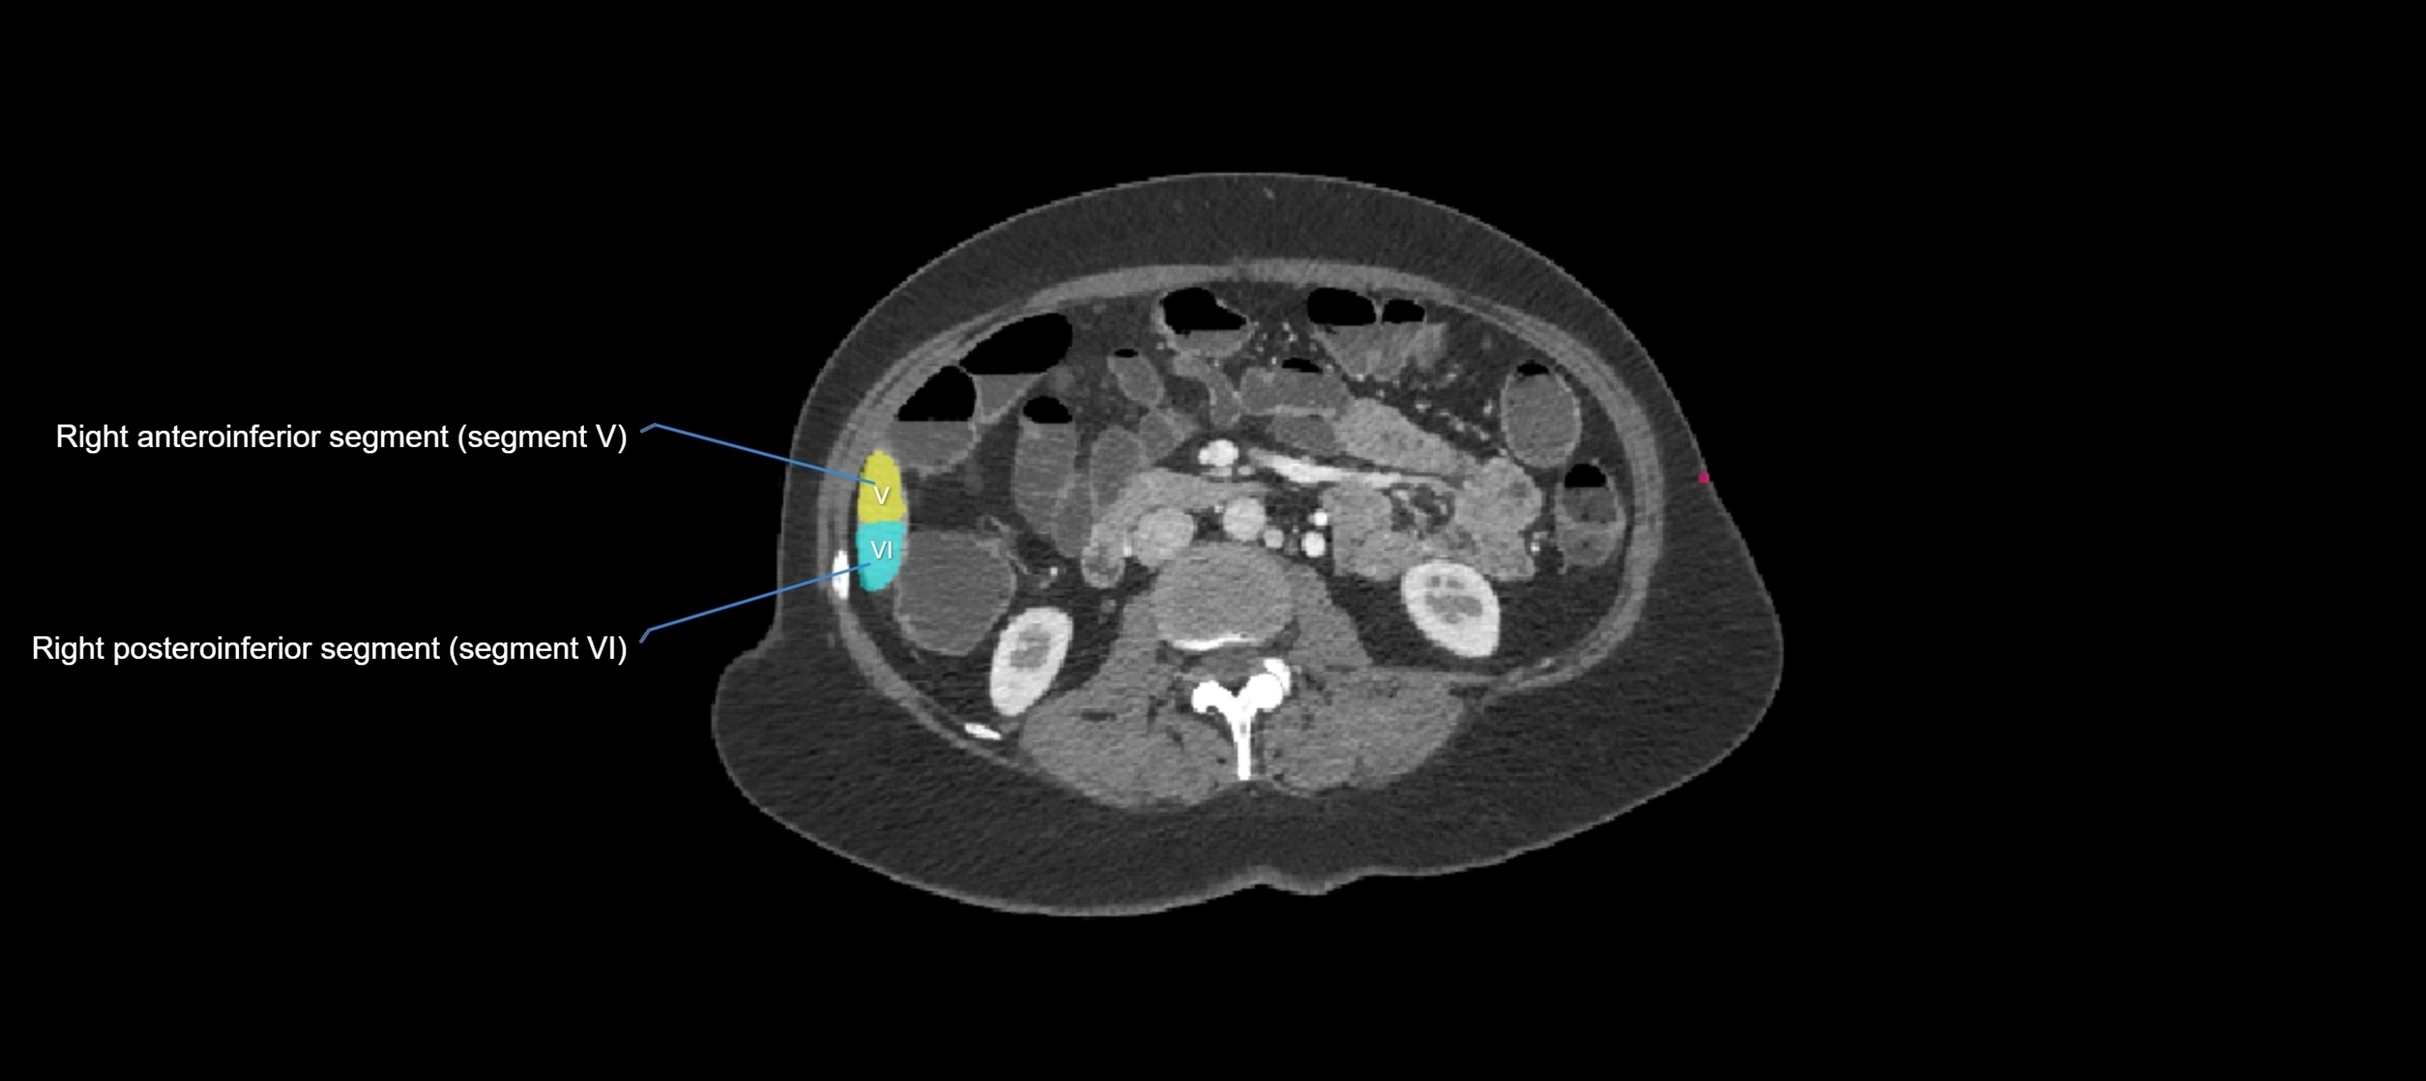

MRI image

image